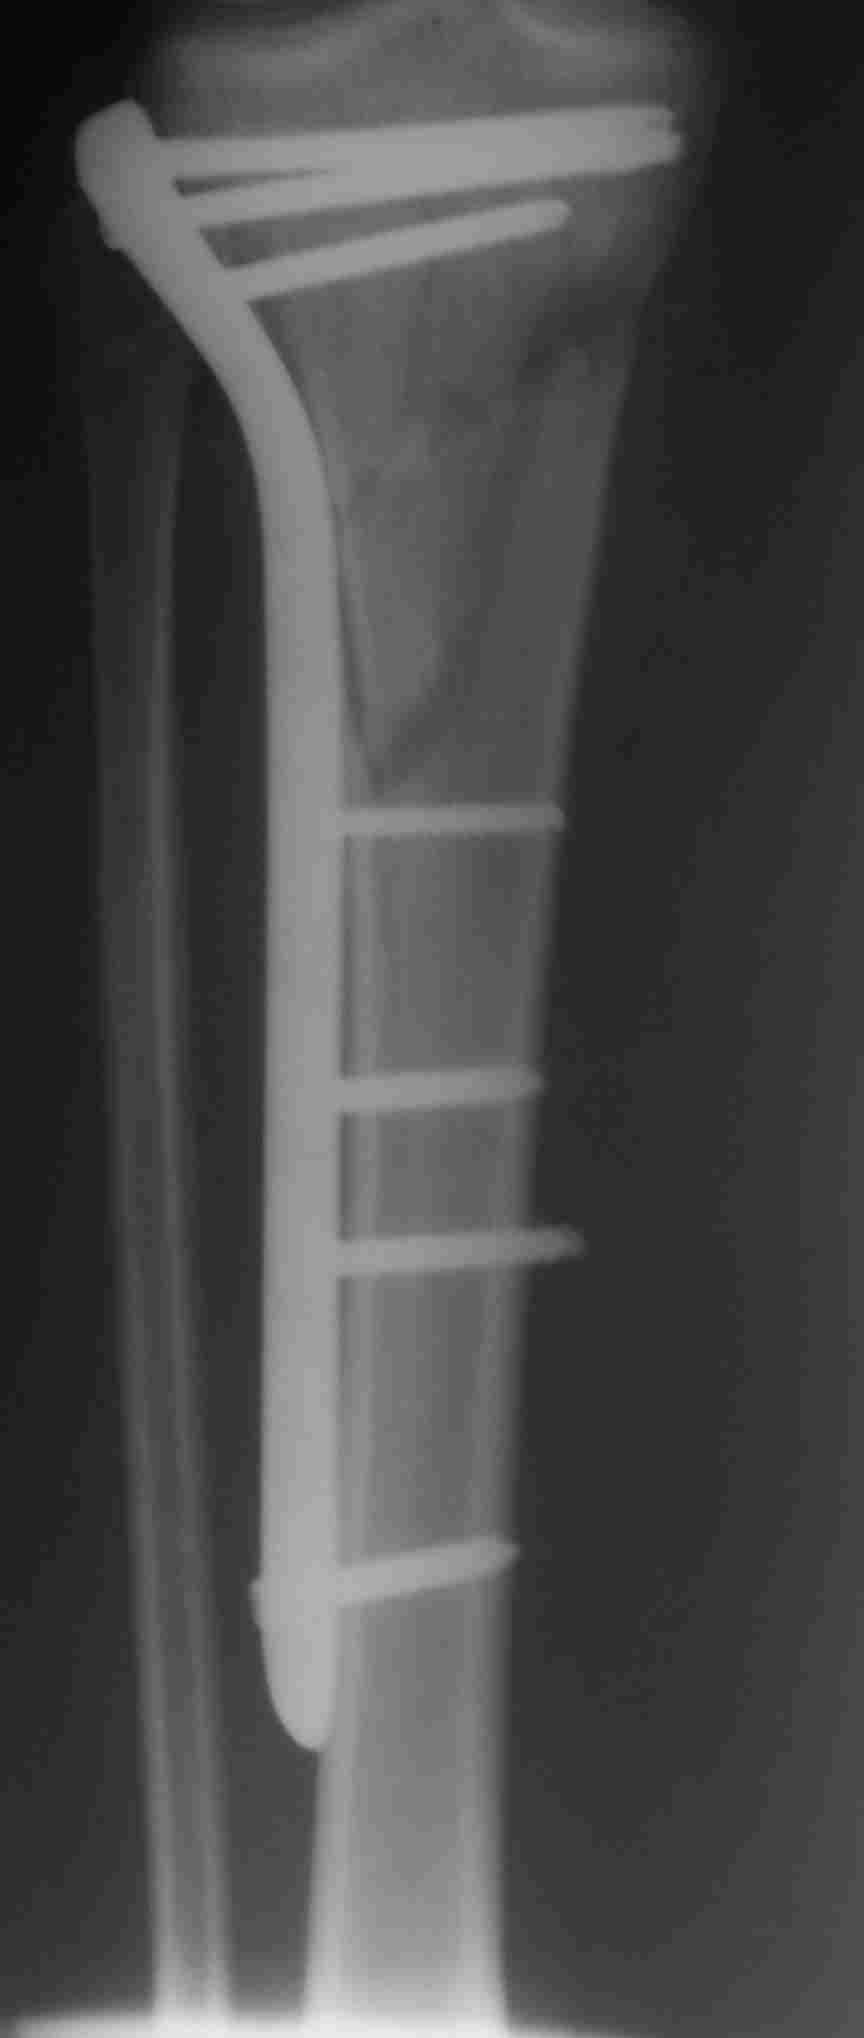

Похожий случай, вчера прооперировали. Непрямая репозиция, малоинвазивный остеосинтез без обнажения зоны перелома.